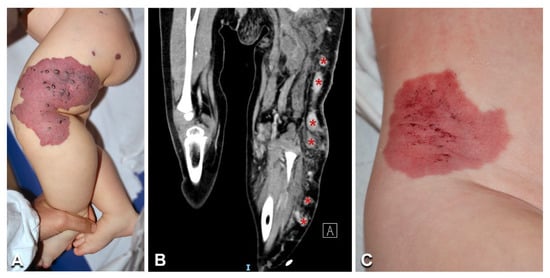

| 15 | 11/M | DCMO | Limb, trunk, and head reticulate CM; right finger and toe macrodactyly | DU: no AVF | PIK3CA | c.1133G > A (p.Cys378Tyr) | 13.5%/nd |

| 16 | 1/M | DCMO | Limb and trunk reticulate CM with centrofacial stain ***; left upper limb overgrowth; sandal gap; triangular foot | DU: no AVF; brain MRI: normal | PIK3CA | c.1093G > A (p.Glu365Lys) | 7%/nd |